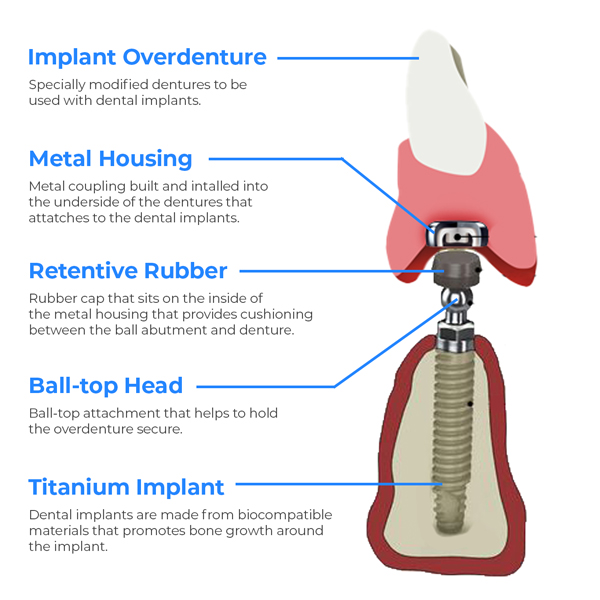

Bar-retained or Ball-retained

When it comes to removable overdentures, there are two different mechanisms for holding them in place.

Ball Retained Overdenture

Ball-retained overdentures consist of a single ball-shaped piece (called an abutment) at the end of each implant. Each ball snaps into a socket in the prosthesis as it attaches.

Bar Retained Overdenture

With a bar-retained implant denture, the abutments are all connected together with a metal bar that runs along the jawline. The benefit of this is that it provides a little more stability and helps spread the biting force more evenly.